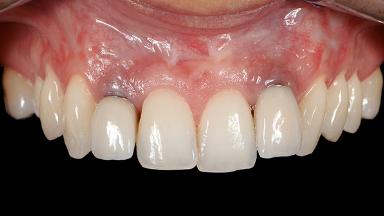

A 30-year-old woman was referred by her general dentist for evaluation of an esthetic complication related to previous implant treatment for congenitally missing maxillary lateral incisors. The patient’s chief complaint was the inadequate esthetic appearance of her smile. The case demonstrates the use of a combined approach to achieve optimal results. Two different flap designs - a tunnel technique and a coronally advanced flap - are employed based on the surgical objectives for the affected site.

Soft Tissue Grafting Yes

Soft Tissue Anatomy Intact Defective